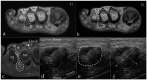

Background: Intermetatarsal bursitis (IMB) is emerging as a diagnostic consideration for patients with forefoot pain. However, few investigations have been conducted into the incidence of IMB among patients with forefoot pain. The symptoms of IMB are described as mimicking those of Morton's neuroma (MN). Currently, the best method to differentiate between MN and IMB is radiological evaluation. Based on this, the aim of this study was to investigate the incidence of IMB and MN in a prospective cohort of patients with intermetatarsal pain diagnosed with radiological evaluation and compared to a control group. Methods: This study included 26 patients and 13 controls. All participants underwent magnetic resonance imaging (MRI) and ultrasound (US) of one forefoot. Results: Among the 26 patients, 5 (19.2%) had MN and 14 (53.8%) had IMB on MRI compared to US, with which 25 (96.2%) cases of IMB and 0 with MN were identified. In the control group, both modalities found asymptomatic web space pathology in four cases (30.8%), and US identified normal intermetatarsal bursas in five cases. Additionally, our results indicate that MN patients have more severe pain and a longer history of pain compared to IMB patients. Conclusions: Based on our MRI results, we conclude that IMB is frequent in patients with intermetatarsal pain. Differentiation between MN and IMB with US is complex and should be performed with caution and an understanding of both conditions. Normal intermetatarsal bursas are also visible on US as hypoechoic but non-expansive masses.